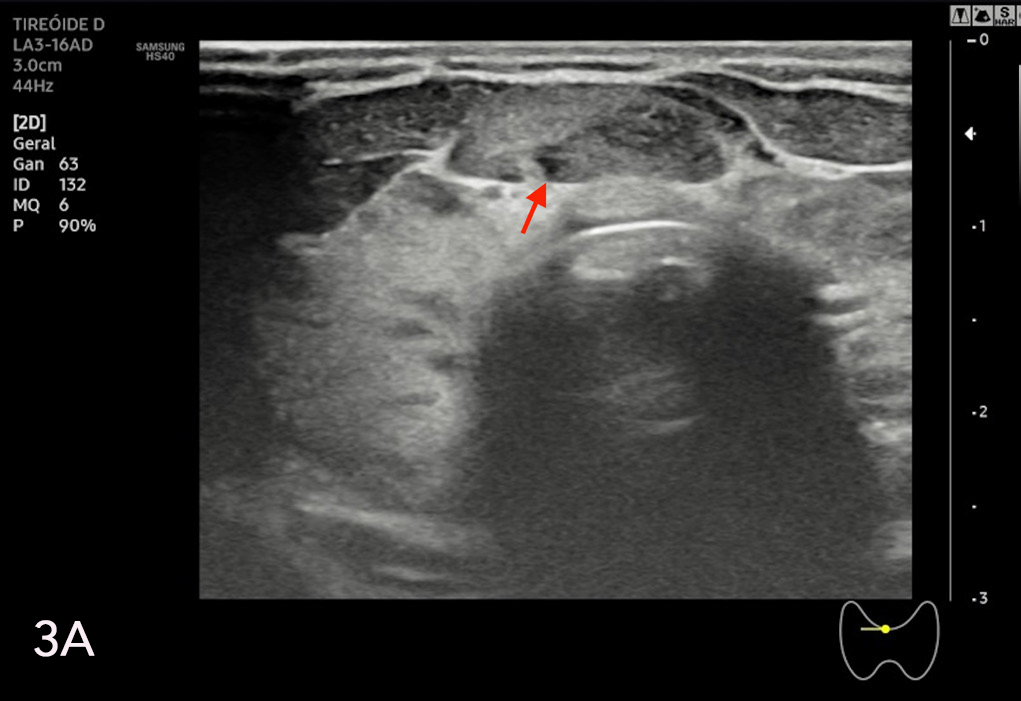

La eco estructura es homogénea, los márgenes son regulares y presenta una cápsula ecogénica, su vascularización es escasa. El rango de referencia para una tiroides normal es de entre cinco y diez vasos visibles dentro de la exploración de cada lóbulo valorado con Doppler color2. Se ha descripto que hasta un 50% de los individuos presentan lóbulo piramidal (Figura 3a y 3b). Este sector, en general, es similar en ecogenicidad, homogeneidad y vascularización al istmo y los lóbulos. En la superficie posterior de los lóbulos tiroideos, especialmente en el segmento inferior, puede visualizarse el tubérculo de Zuckerkandl, un ejemplo de este se puede observar en la figura 4a y 4b. Este es un tabique hiperecogénico fibroso que a menudo genera sombra posterior. Se forma por la extensión del tejido tiroideo de las áreas laterales de los lóbulos hacia el sector posterior, y a menudo exhibe una disminución de la ecogenicidad detrás del mismo. Este proceso puede imitar una lesión tiroidea o paratiroidea y causar dificultades en la interpretación2.